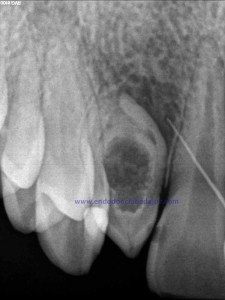

Nuestro caso, se trataba de esta pieza con necrosis pulpar con afectación periapical que presentaba una vía de drenaje (fístula). Esta radiografía muestra el camino de la fístula a la lesión apical.